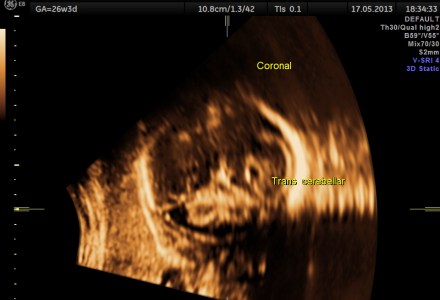

CEREBELLAR HYPOPLASIA POSSIBLY DUE TO CARBAMAZEPINE

SPINA BIFIDA -OPEN NEURAL TUBE DEFECT 3D IMAGES

NEURAL TUBE DEFECT